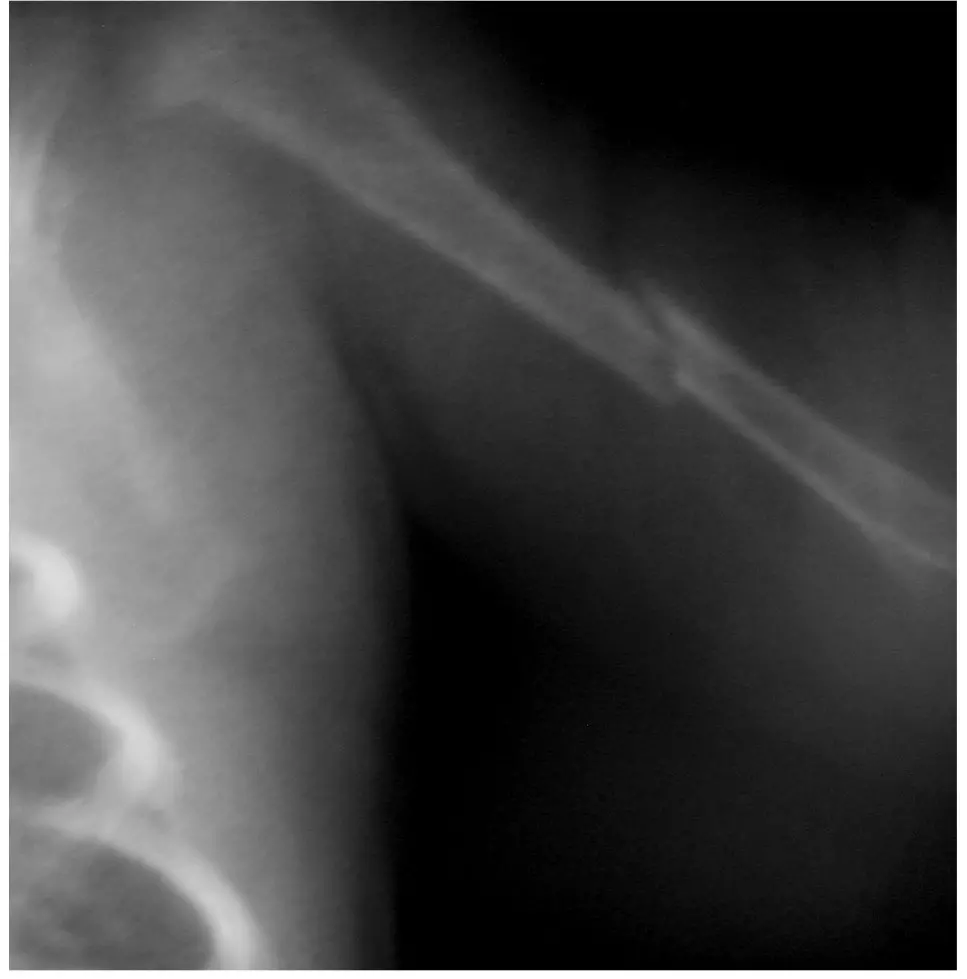

3,5-miesięczny wcześniak urodzony w 32. Hbd, z masą ciała 700 g, z obciążonym okresem noworodkowym (długotrwała mechaniczna wentylacja, BPD, długotrwałe żywienie pozajelitowe, cholestaza, nietolerancja karmienia) został przyjęty do naszej kliniki z powodu podejrzenia ciężkiej postaci krzywicy. Dziecko karmione Bebilon pepti MCT, otrzymywało 1500 IU/d witaminy D. Dwa tygodnie przed przyjęciem do kliniki doszło do obustronnego złamania trzonów kości udowych (w odstępie kilku dni) oraz złamania trzonu lewej kości ramiennej (ryc. 1, ryc. 2). W rejonie rozpoznano krzywicę z niedoboru witaminy D i włączono do leczenia witaminę D,

Ryc. 1. Świeże złamanie trzonu kości ramiennej u dziecka z osteopenią wcześniaczą

Ryc. 3. Świeże złamanie trzonu kości udowej u dziecka z osteopenią wcześniaczą